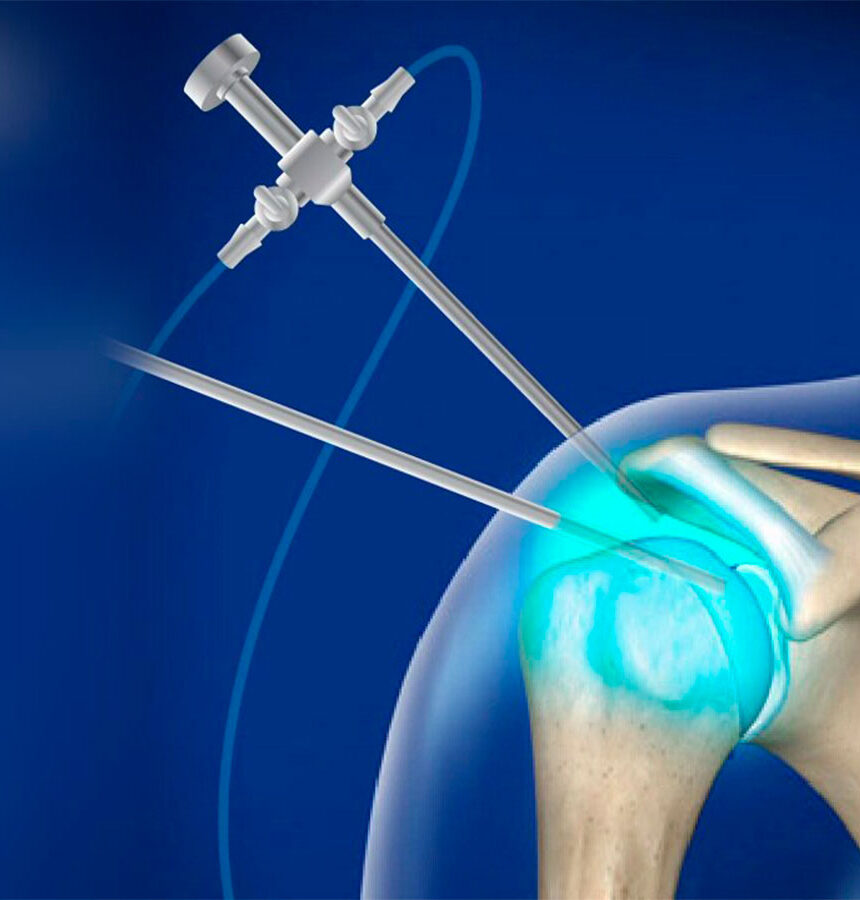

Tenía un dolor tremendo en el hombro que no me dejaba dormir de un lado. Hoy ya no tengo problema para descansar de ningún costado y me siento muchísimo mejor. Después del tratamiento con plasma rico en plaquetas, la diferencia es enorme: nada que ver con lo que era al principio. Puedo mover el brazo con normalidad, incluso hacer gestos cotidianos como peinarme. Gracias, Dr. Ciladi.

Lina